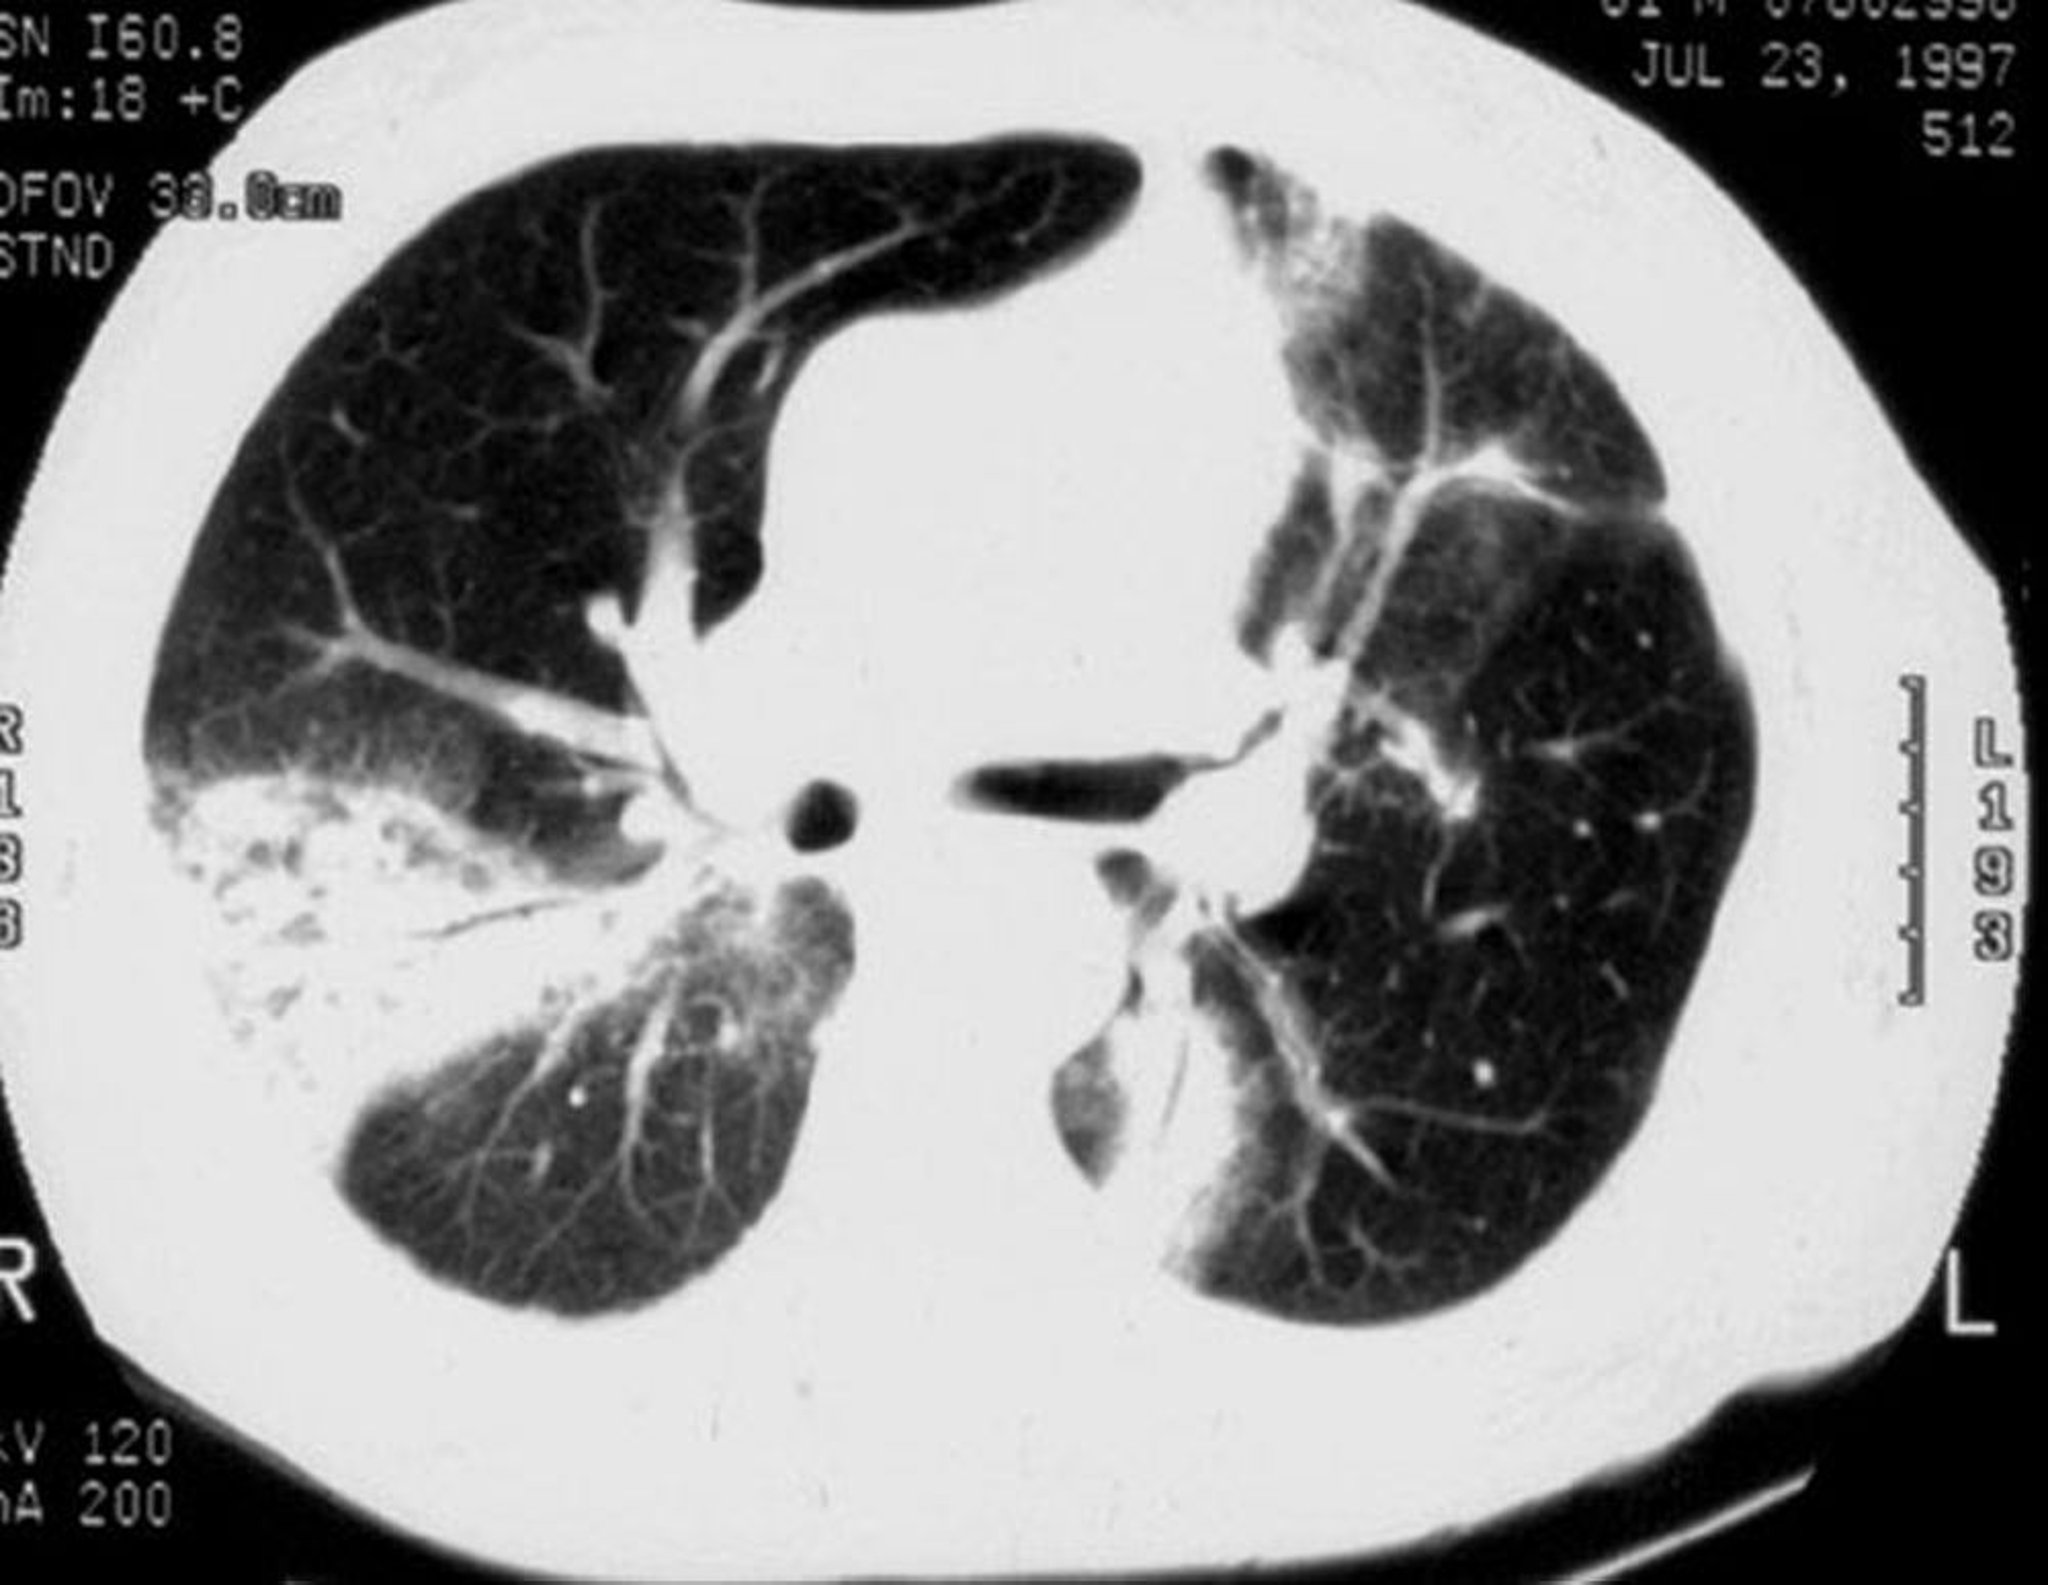

La TC ad alta risoluzione mostra addensamenti a chiazze degli spazi aerei polmonari (presenti nel 90% dei pazienti), opacità a vetro smerigliato, piccole opacità nodulari e ispessimento e dilatazione delle pareti bronchiali. Le opacità a chiazze sono più frequenti nella periferia del polmone, spesso nei campi inferiori. La TC ad alta risoluzione può mostrare una malattia molto più estesa di quanto ci si aspetti dalla RX torace. Possono essere notati piccoli versamenti pleurici. Il segno dell'alone invertito (bordo di consolidamento con chiarezza centrale) è raro ma sembra essere relativamente specifico per la polmonite organizzativa.

La TC ad alta risoluzione mostra addensamenti a chiazze degli spazi aerei, opacità a vetro smerigliato, piccole opacità nodulari e ispessimento e dilatazione delle pareti bronchiali (broncogramma aereo).

Image courtesy of Talmadge E. King, MD.